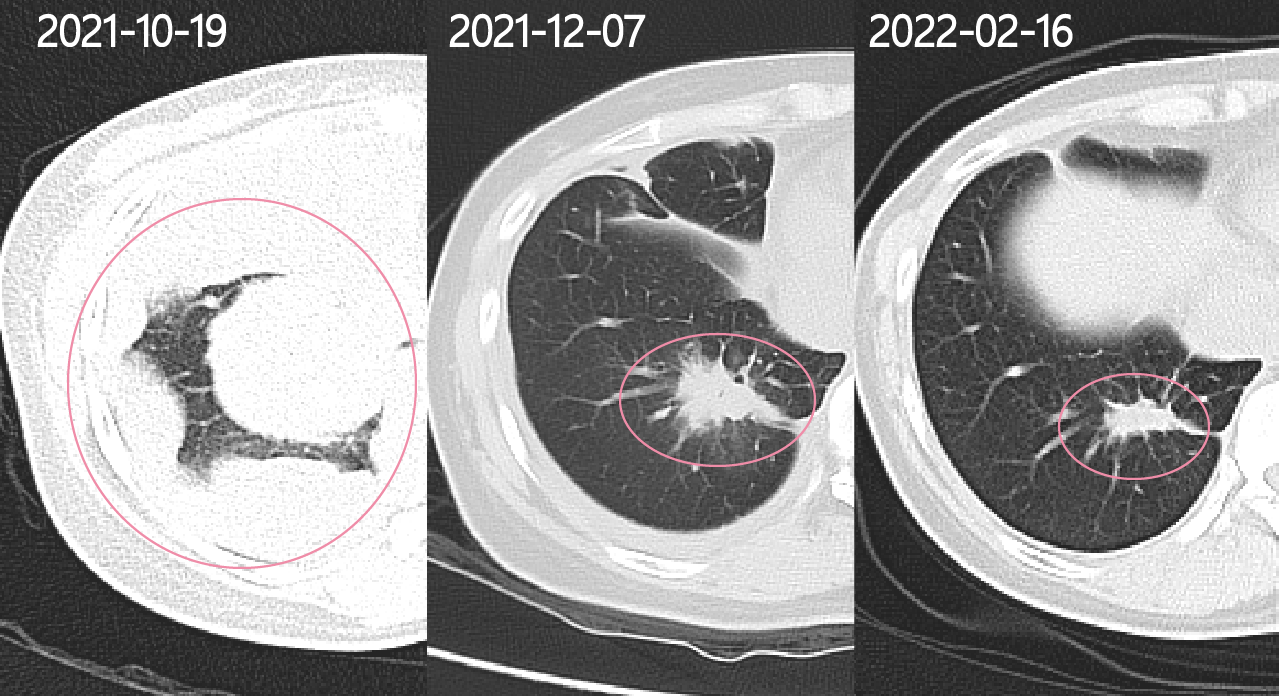

从第一粒奥希替尼到现在一百多天肿瘤持续缩小,一开始整个右侧胸腔就像放满了包子,现在只剩一粒花生米,影像上看胸壁已经光滑圆润。

5.48*5.4cm到1.8*1.8(奥希替尼35天)再到1.4*0.9(奥希替尼108天),